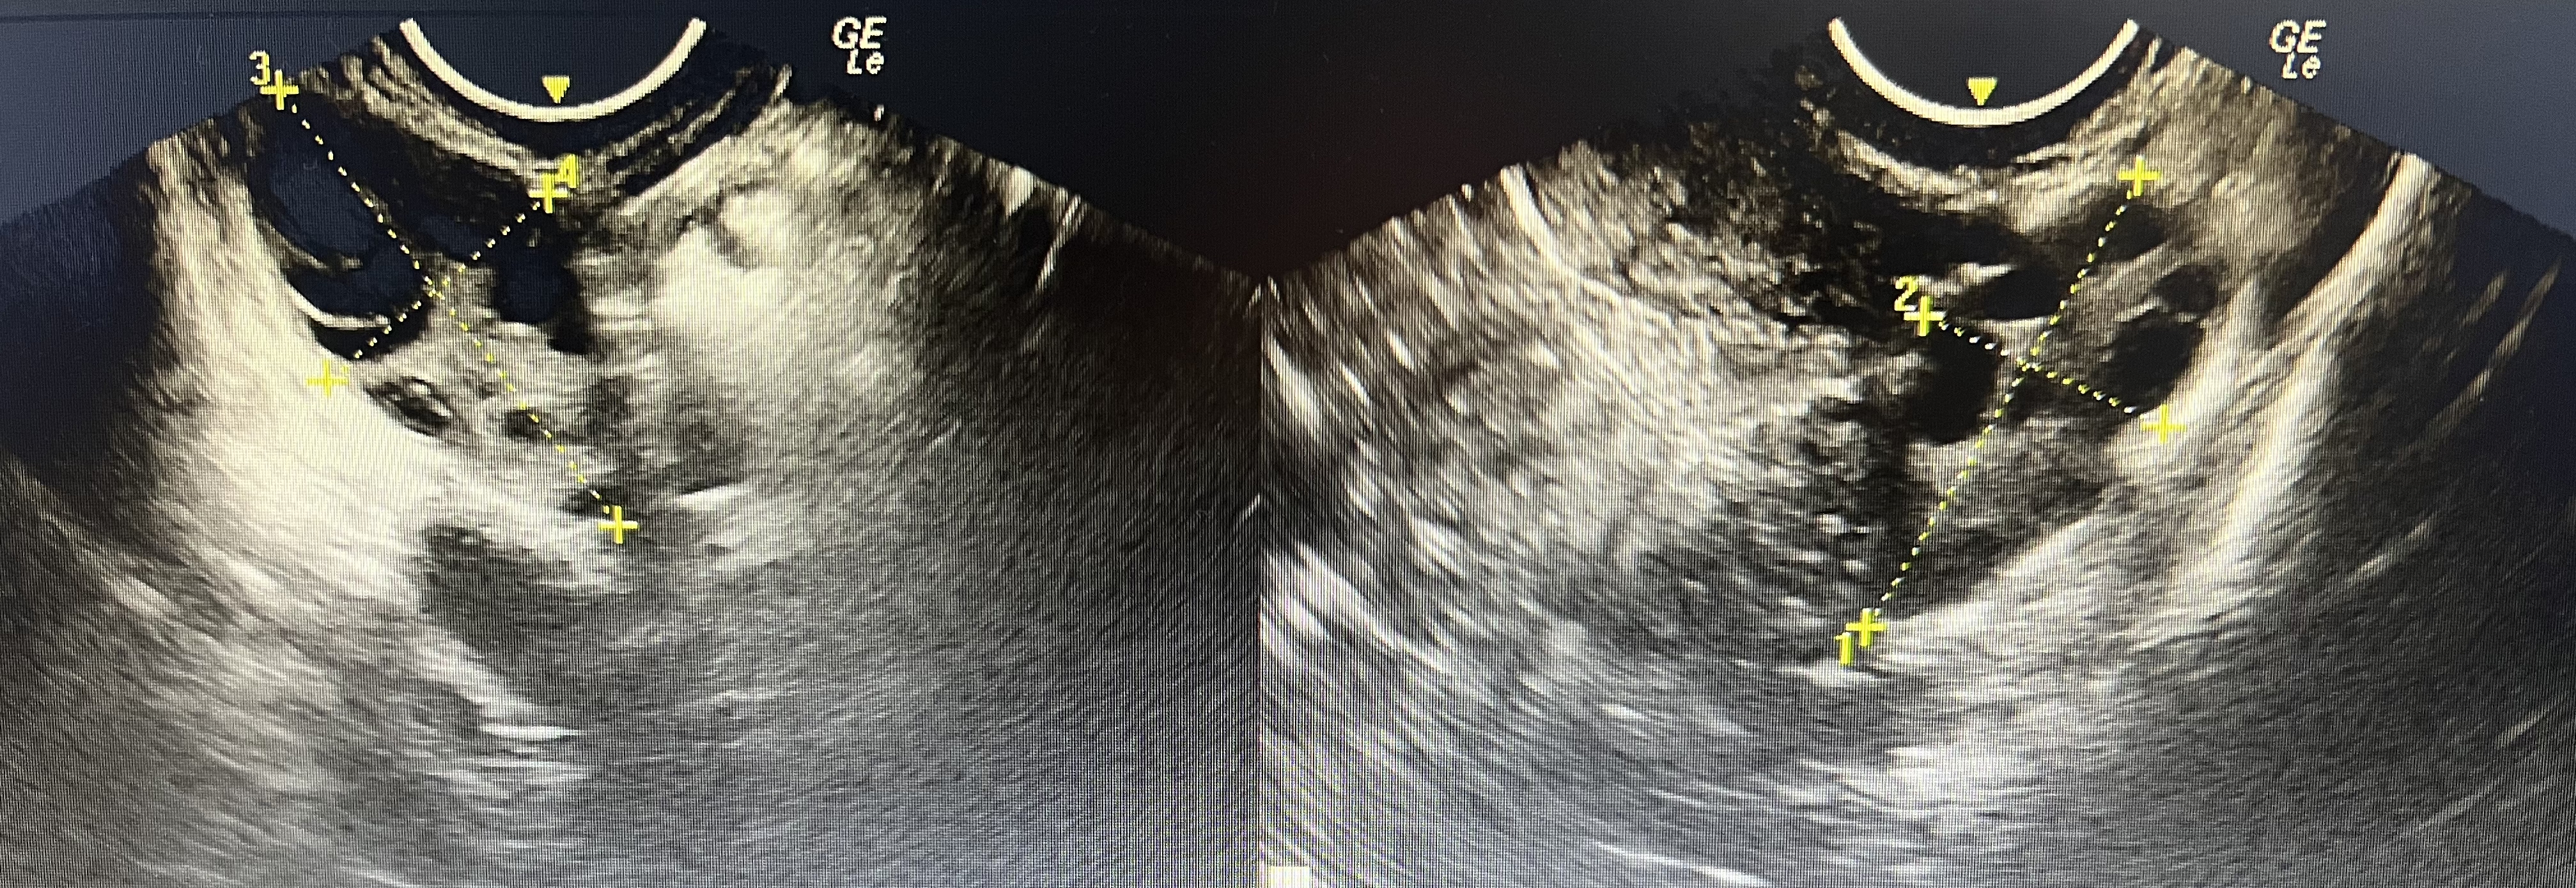

2、妇科B超:卵巢多卵泡改变。

妇科经阴道超声出现双侧卵巢多卵泡改变(一圈小卵泡,像项链一样,形成“项圈征”)无成熟大卵泡,故排卵障碍。